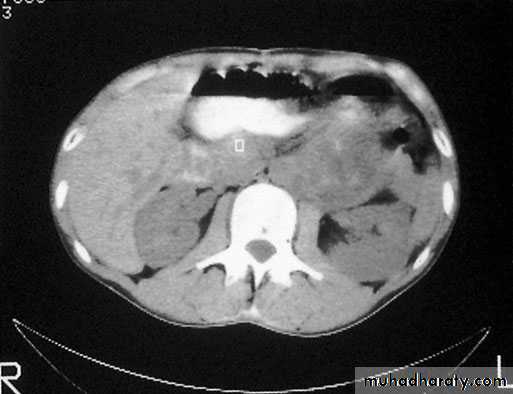

CT scan and MRI are the most useful means of detecting secondaries and f monitoring the response to therapy.

Scrotal Pathologies